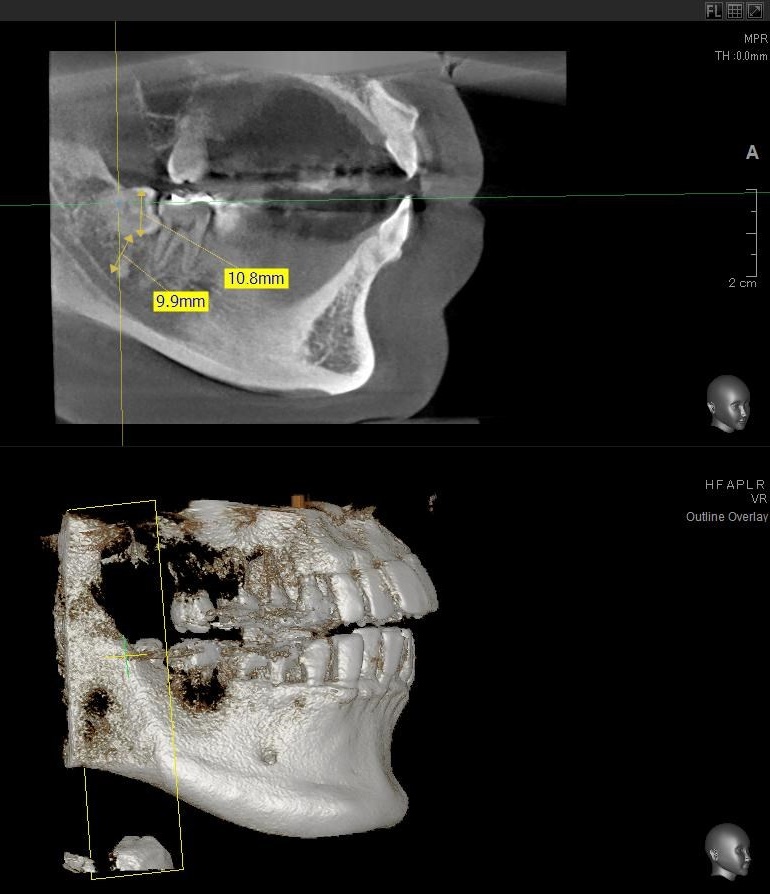

次にパノラマ写真を撮影してみると、右下の親知らずは手前の歯の歯を押すように斜めに生えているのが確認できました。

さらに、下顎の親知らずは下歯槽神経に非常に近いところに生えている場合もあるため、CTも撮影し詳しい解析を行います。

親知らずの根っこは下歯槽神経から近い距離にありますが、抜歯は可能との診断でした。